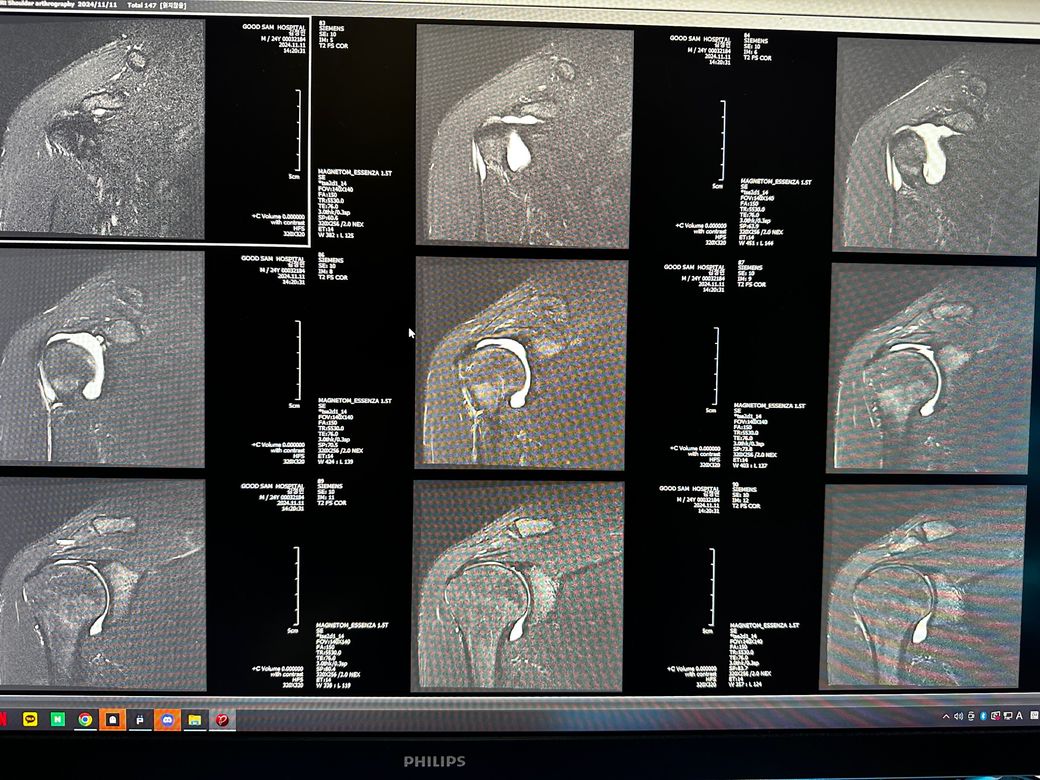

오른쪽어깨 관절mri좀 봐주세요 사진첨부입니다

오룬쪽어깨관절 엠알아이 결과좀 봐주세요

오른쪽어깨관절부분입니다

관절입니다

• 4번 째 사진

• 5번 째 사진

• 6번 째 사진

조영제가 들어간 것으로 보이며, "회전근개(특히 극상근) 파열이나 큰 손상은 뚜렷하게 보이지 않는 편"입니다.

관절와순(Labrum) 주변에 조영제가 퍼져 보이지만, "명확한 파열 소견은 사진만으로 단정 어렵고 경미한 손상.염증 가능성"은 있습니다.

관절 안쪽에 "약한 염증/활액 증가"는 있어 보이며, 충돌증후군 초기 형태 가능성이 있습니다.